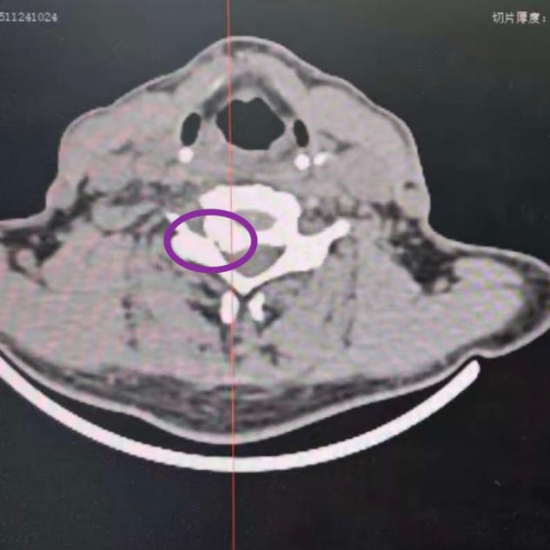

CT影像显示严重的神经根管狭窄